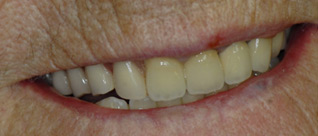

J’ai des vieilles couronnes et des bridges à refaire, je refuse l’appareil mobile. On reprend la totalité du sourire et on place des dents fixées sur implants.

J’ai une ou plusieurs dents qui manquent que je veux remplacer mais sans toucher aux autres.

Solution : on va remplacer ces dents par la mise de un ou plusieurs implants.

Un grand bridge supérieur à refaire, le patient veut des dents individuelles.

J’ai un appareil amovible du bas que je ne supporte plus, je veux des dents fixées.